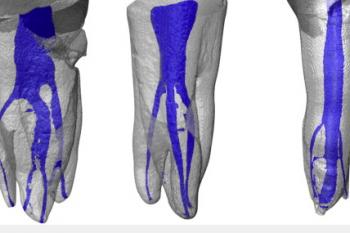

Conventional intra-oral radiography provides clinicians with cost-effective, high-resolution imaging that continues to be the front-line method for dental imaging. However, it is clear that there are many specific situations where the 3-D images produced by CBCT facilitates diagnosis and influences treatment. The usefulness of the CBCT cannot be disputed. It is a valuable task-specific imaging modality, producing minimal radiation exposure to the patient and providing maximal information to the clinician.

The introduction of the surgical operating microscope (SOM) to endodontitcs has dramatically changed the practice of the specialty. The microscope, within the last two decades has revolutionized the way procedures are performed. Each root canal therapy and examination is performed with the Zeiss OPMI Microscope. With the Zeiss OPMI Microscope, details and fine structures are clearly visible at high magnification levels. It enables the operator to better visualize the regions of interest and consistently provide patients with high-quality examinations and treatments.